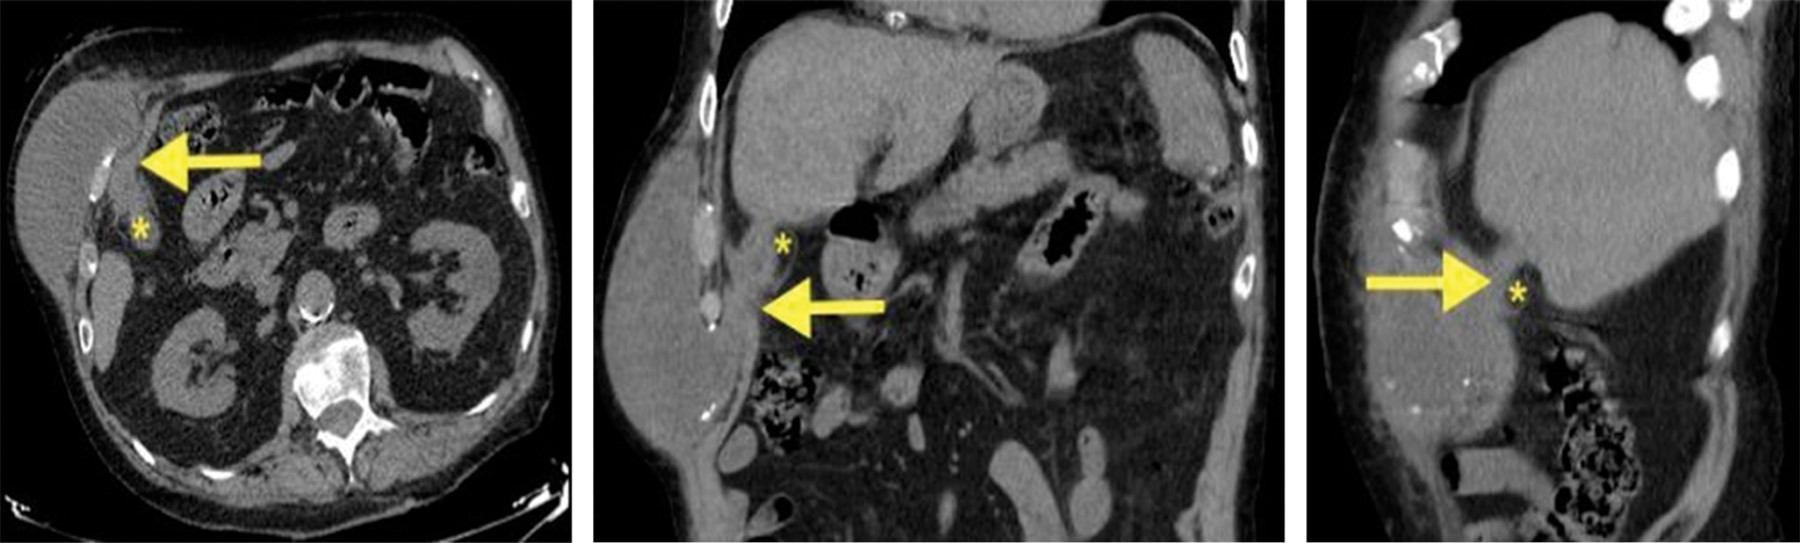

Caso 2. Hombre de 87 años dependiente para las actividades básicas de la vida diaria (ABVD). Antecedentes de miastenia gravis, hipotiroidismo, vasculopatía con isquemia crónica de extremidades inferiores y un infarto de miocardio, así como un episodio de colecistitis aguda tratado de forma conservadora cinco años antes. Consultó por una tumoración indolora en el HCD de año y medio de evolución, con supuración espontánea durante la última semana. A la exploración presentaba un diámetro de 20 cm y una pequeña solución de continuidad. La TC informó de colecistitis crónica litiásica complicada en continuación con un absceso en la pared abdominal y fistulización a la superficie cutánea (Figura 2).

Se optó por DP del absceso y tratamiento AB. La colangiorresonancia magnética (col-RM) posterior informó de una pequeña colección líquida de 4 × 1 cm en la pared abdominal anterosuperior derecha con pequeños cálculos biliares en su interior, vesícula biliar colapsada con colelitiasis y sin clara evidencia de fístulas, además de ausencia de alteraciones en la vía biliar intra y extrahepática. El débito escaso, pero mantenido a través del drenaje, motivó el mantenimiento de éste, hasta que a las cuatro semanas presentó salida accidental, por lo que se decidió no recolocarlo. La evolución posterior fue favorable. Se desestimó el tratamiento definitivo por su elevado riesgo anestésico.